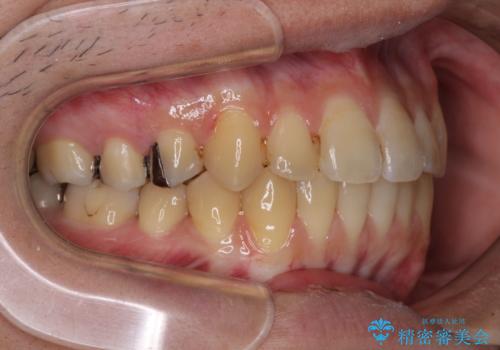

前歯のクロスバイトをインビザラインで矯正治療

- 前歯のデコボコとクロスバイトを気にして来院された患者様です。

前歯を早く整えたいとの希望があったので、ワイヤー矯正にて短期間でクロスバイトを解消し、その後インビザラインにて整えることとしました。

インビザラインによる前歯のクロスバイト改善におけるリスクとして、前歯歯髄充血・歯髄壊死が挙げられます。

ワイヤー矯正を併用する目的として、短期間でデコボコやクロスバイトを改善する他に、歯髄充血リスクを低減させるというものがあります。